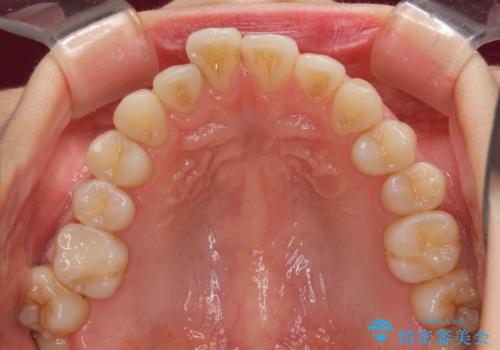

- 上下前歯のデコボコを気にして来院された患者様です。

インビザラインによる上下歯列の側方拡大と後方移動、IPR(歯と歯の間を削る)にるスペースの獲得により歯列を整えることとしました。